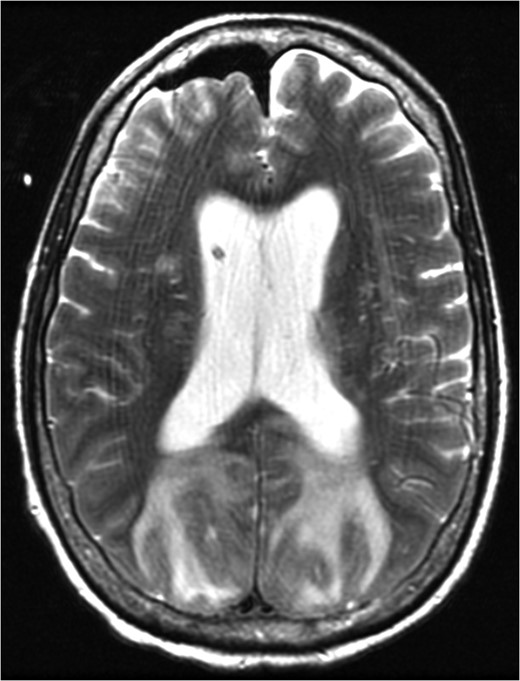

MRI brain at the time of diagnosis, Axial T2 sequence. Vasogenic edema involving the bilateral cerebral hemispheres, with relative sparing of the frontal lobes suggestive of PRES. Pneumocephalus is present secondary to interval placement of an external ventricular drain (seen in the right lateral ventricle).